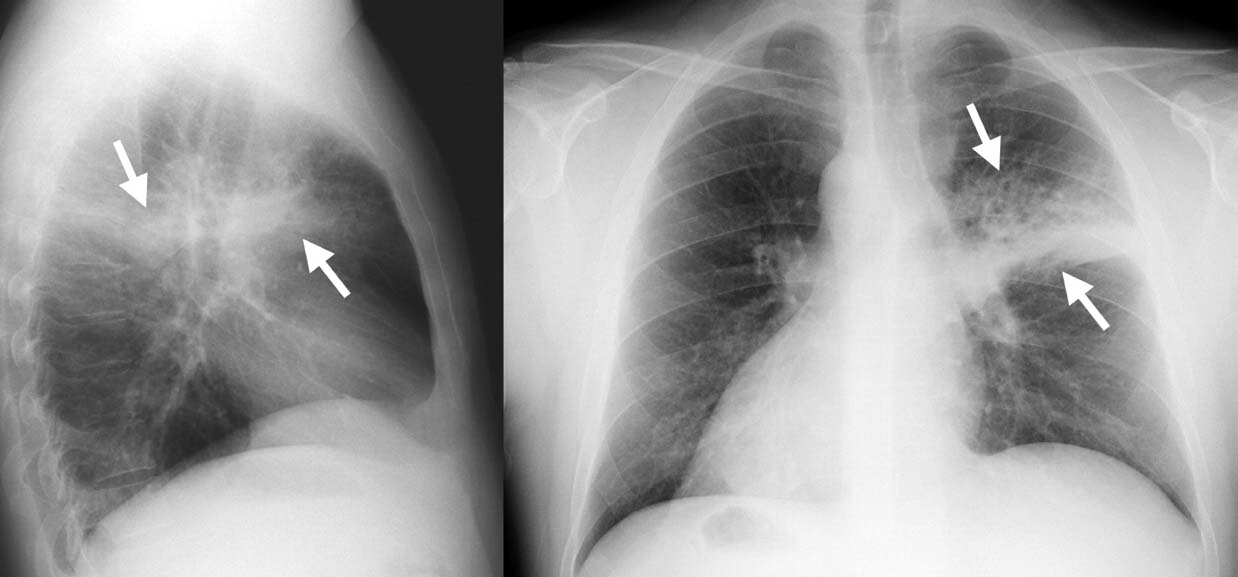

Основную роль в постановке окончательного диагноза отводят рентгену грудной клетки.

Пневмония на рентгеновском снимке

На снимках, полученных после рентгенологического исследования, отмечается усиленный сосудистый рисунок, участки потемнения легочной ткани и рассеянная перибронхиальная инфильтрация.